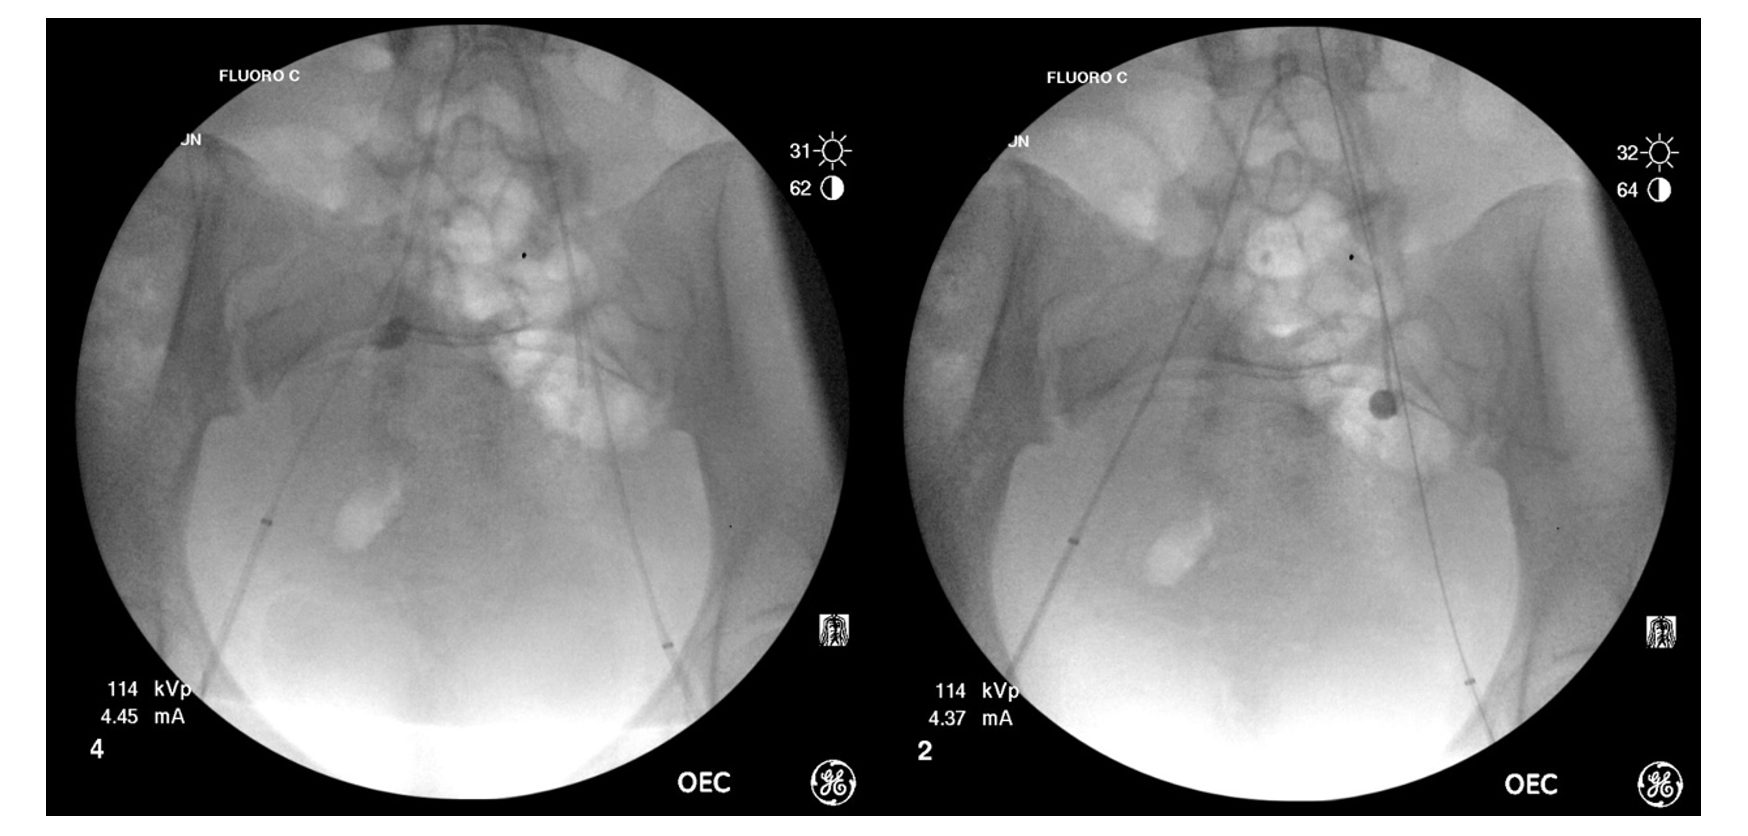

The procedure was performed in the operating room. Initially, the patient was placed supine. With the use of an ultrasound and C-arm for fluoroscopy, bilateral femoral arterial access was obtained, and 6F sheaths were placed. A 5F Cobra 2 catheter was used to cross the aortic bifurcation to the contralateral internal iliac artery (IIA). The catheters were then exchanged over a regular 0.035" Glidewire (Terumo) for 5.5F Fogarty balloons (Edwards Lifesciences), positioned in the proximal IIAs (Figure 2 and Figure 3). Test inflation of the balloons was performed under fluoroscopy to determine balloon volume required for vessel occlusion. The balloons were deflated, and the catheters and sheaths were well-secured. The patient was then shifted into lithotomy position and uterine vacuum aspiration was performed by the gynecology team. Following evacuation, bilateral angiograms were performed and demonstrated no active bleeding. Total estimated blood loss for the combined procedure was 20 mL. The patient remained in the hospital overnight for pain control and was discharged the next day. At postop day 5, a telephone follow-up was completed and the patient reported she was doing well.